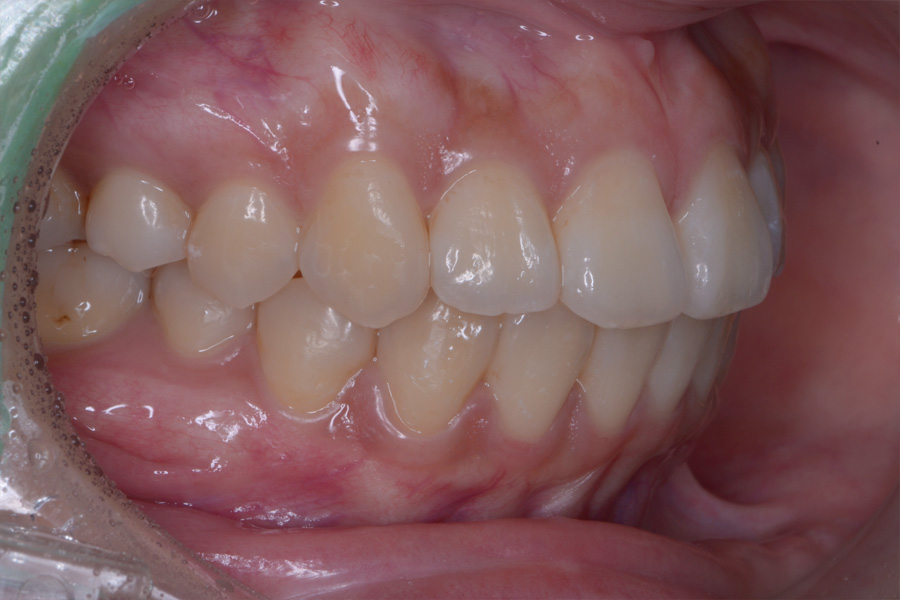

【20代女性】

飛び出ている2本の歯を引っ込めて

下の捻じれている歯を並べたい

治療後

主訴 飛び出ている2本の歯を引っ込めて下の捻じれている歯を並べたい

治療内容 ハーフリンガル矯正(上顎裏側・下顎表側矯正)